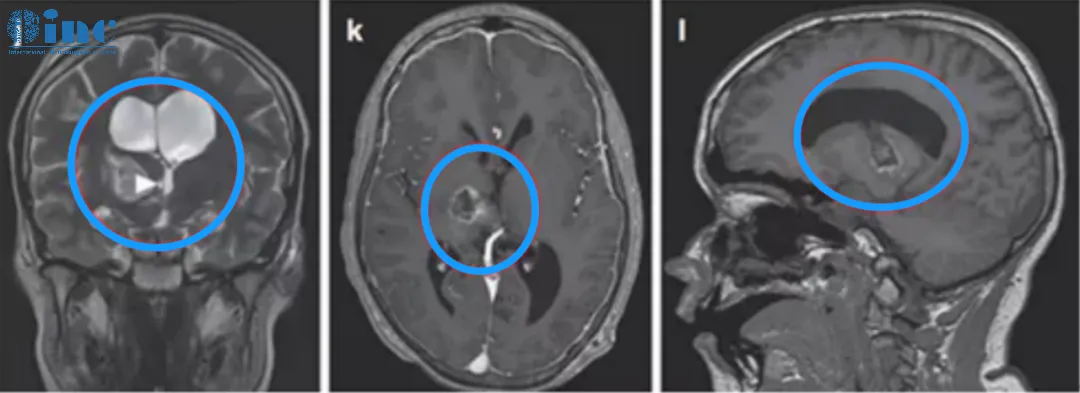

26岁足球运动员巨大丘脑占位次全切后10天出院

患者情况:在一次头部轻伤后近3个月来逐渐出现复视、肢体活动欠灵活、容易急躁,遂当地医院就诊。发现巨大丘脑占位并压迫脑干,当地医院表示,目前虽无明显肢体瘫痪症状,但是手术难度风险极大,有昏迷、失明、术后瘫痪、感觉障碍等可能,且肿瘤切除率有限。后慕名求诊于德国巴特朗菲教授。

诊断:右侧丘脑胶质母细胞瘤(胶质瘤4级),压迫右侧中脑WHO 4级,MGMT甲基化。

主刀医生:INC巴特朗菲教授

治疗后情况:在术中电生理监测(SEP和MEP)下,巴特朗菲教授采用右侧额叶旁开颅术和通过额叶纵裂经胼胝体入路,肿瘤得到次全切除。手术顺利,无围手术期并发症。术后当天拔除气管,无神经功能缺损。术后第2天转到普通病房。术后左手有轻微精细运动欠灵活,术后1周左右明显改善。术后10天出院,保持清醒,精神可,没有颅神经缺损;没有视野缺陷,肢体感觉和运动正常。

术后MR显示肿瘤次全切除,占位效应明显解除